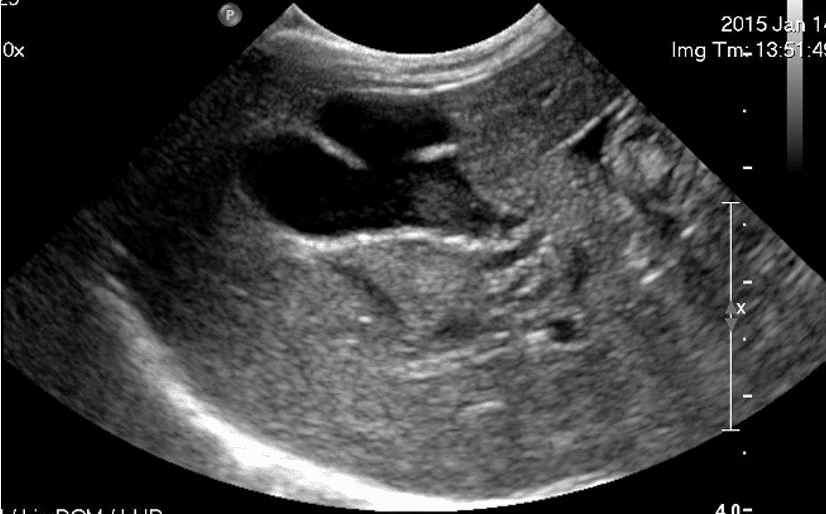

Aisha completed a veterinary degree at the University of California: Davis. Following an internship, she commenced on a path to specialization in radiology. This led to a residency program at the University of Prince Edward Island in Canada, where she acquired her certification as a Diplomate of the American College of Veterinary Radiology (DACVR). Aisha worked as a radiologist in the US and Canada, as well as at the University of Sydney and the University of Melbourne prior to co-founding Vet Waves with Jennifer Kan. Aisha enjoys teaching, particularly in small groups, and has completed a Graduate Certificate in Clinical Teaching (GCCT) to deepen her understanding of teaching and learning. Aisha enjoys all aspects of radiology, but has a particular interest in ultrasound. She has published imaging research to help sea turtles and monkeys, and was drawn to Australia because of its many unique native species and access to the ocean.